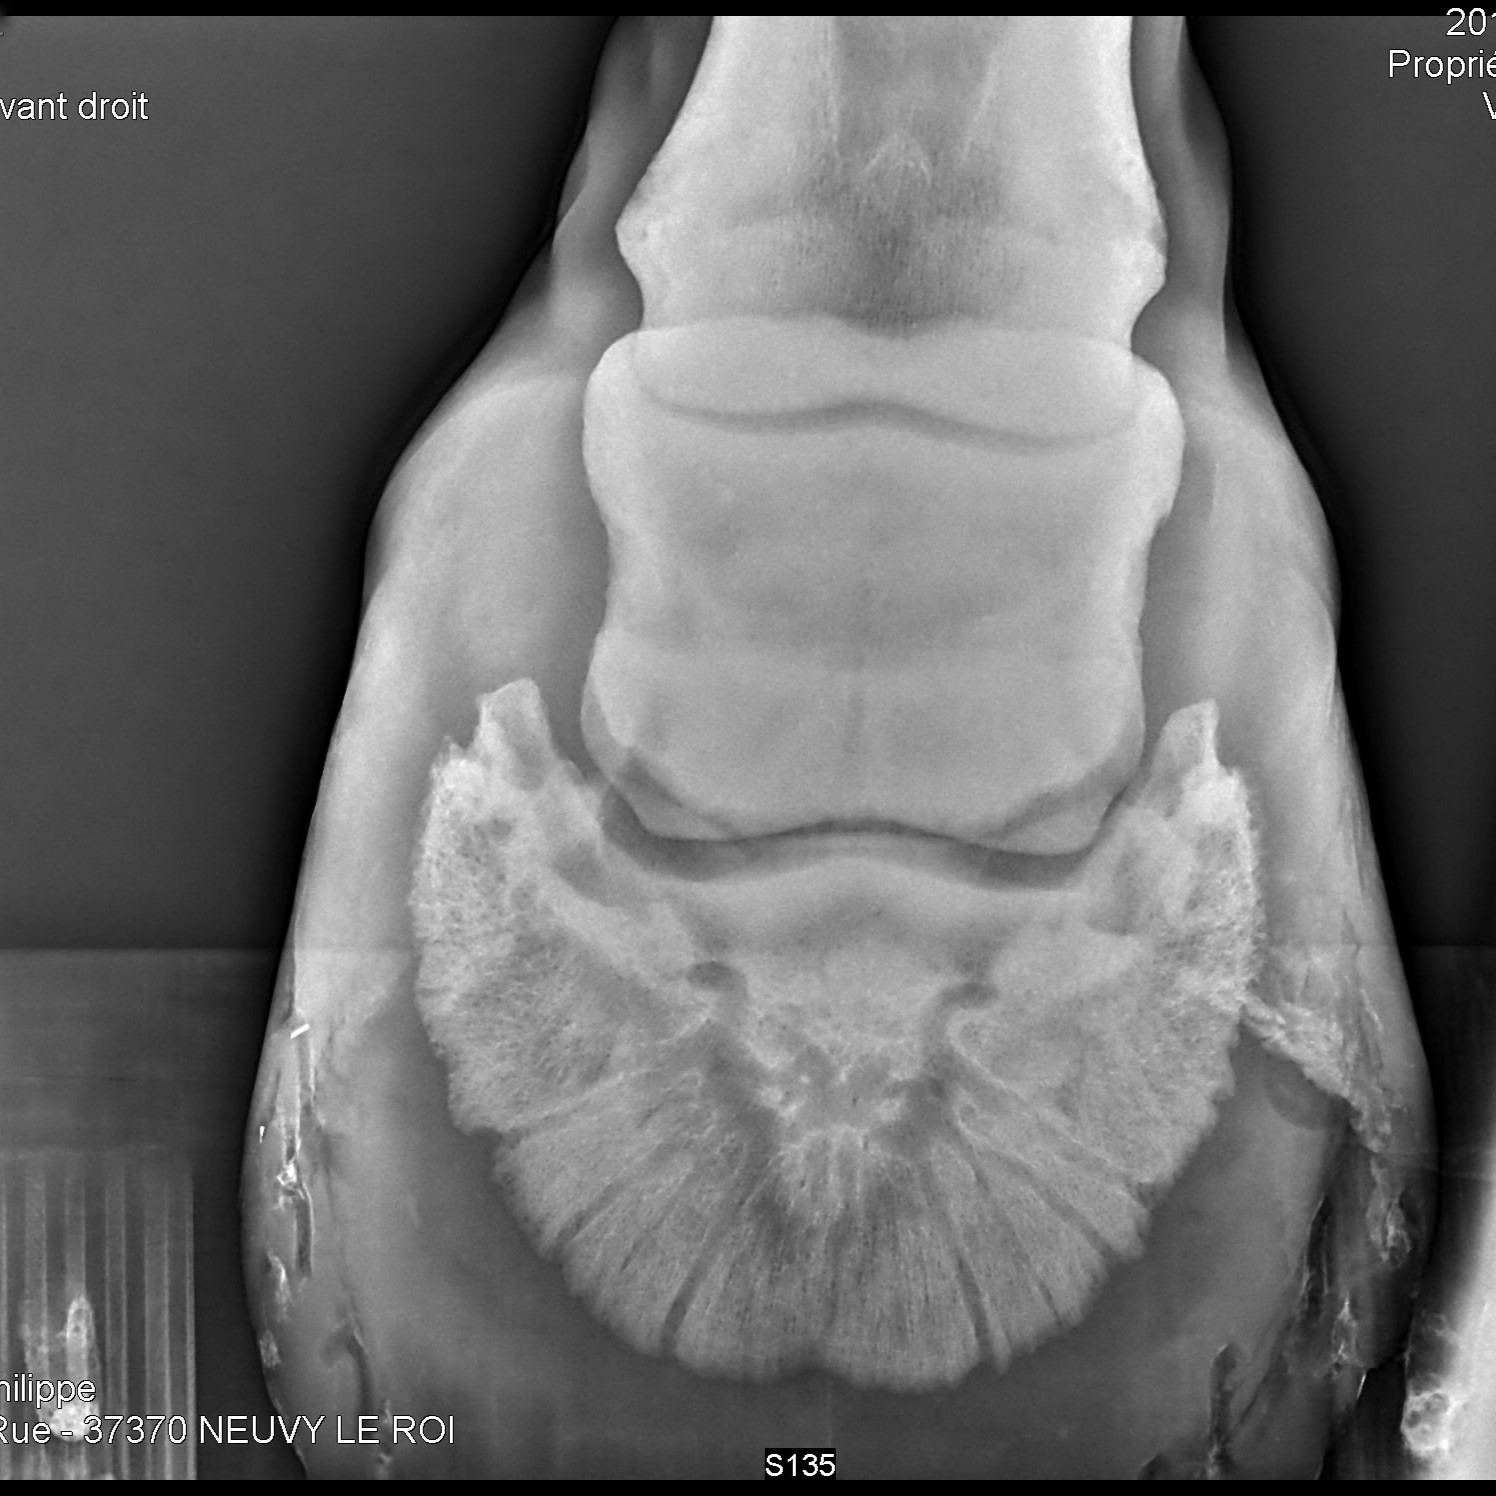

Radiographie des membres

Très utile lors de la recherche de fractures, la radiographie des membres permet également l'évaluation de différents problèmes articulaires tels que l'arthrose ou la dysplasie.

os naviculaire d'un cheval